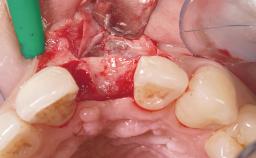

This 43-year-old male patient, a non-smoker, came to our practice because of a fracture of tooth 12 caused by a bicycle accident. Due to the combined para- and infrabony crown and root fracture, tooth extraction, and subsequent implant placement were suggested to the patient as the therapy of choice. The patient had high esthetic expectations with regard to the treatment outcome and asked for an immediate fixed provisional restoration. His individual esthetic risk profile summed up to a medium esthetic risk.

Placement Protocol Immediate implant placement

Tooth Site Maxillary incisor or canine

Socket Morphology Single-root socket

Socket Integrity Sufficient, with intact bone walls